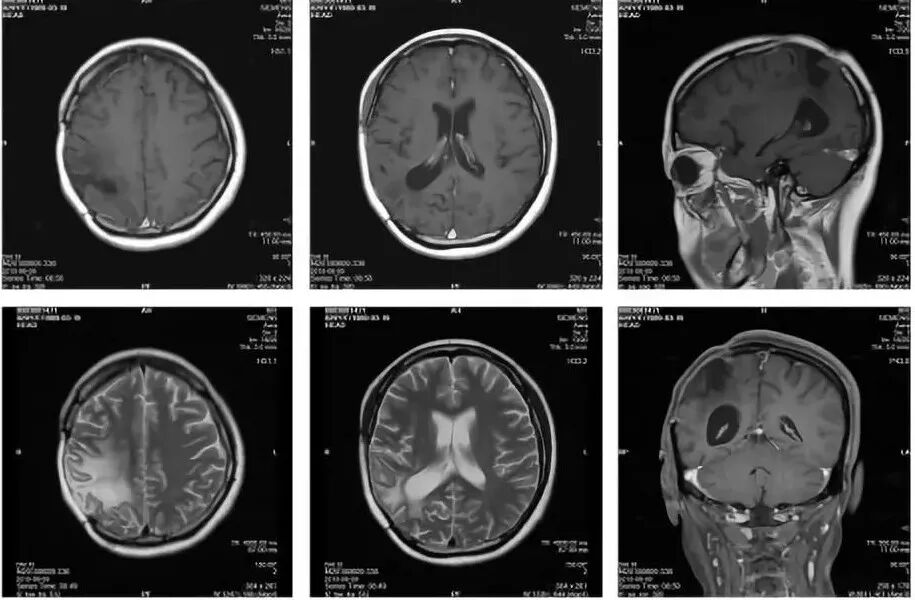

图5. 第二次术后MRI(2017.3.30)

第二次术后病理结果(图6)仍显示为:胶质母细胞瘤 WHO IV级。

免疫组化结果:GFAP (+),Ki67(30%+),P53(部分+),IDH1(-),H3 K27M(-),Olig2(+),MGMT(部分+)。术后于2017年04月17日-2017年05月28日期间进行同步放化疗(图11)。

图7. 第二次术后2个月复查MRI(2017.5.27)